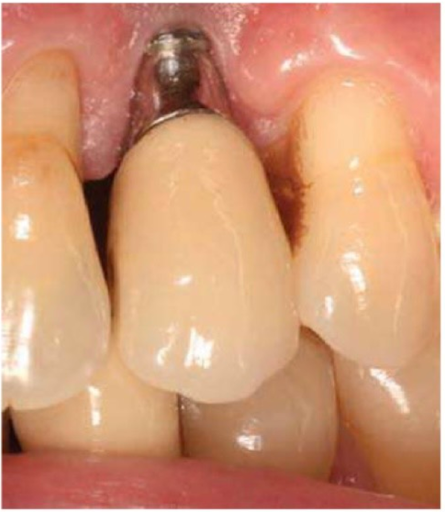

Thiếu hụt viền nướu tại vùng implant răng nanh hàm trên bên trái, lộ vùng abutment gold cùng với đầu implant. Bệnh nhân này có mô nướu mỏng và sự tụt nướu này xảy ra cùng với những vùng nướu răng kế cận.

Điều này có thể dẫn tới tình trạng đau nhức và hệ quả là kiểm soát mảng bám kém. Viêm và đau nhức dai dẳng có thể giải quyết bằng cách ghép niêm mạc sừng hóa cho vùng này theo thủ thuật tương tự như ghép nướu rời sử dụng mô khẩu cái. Trong các trường hợp có mất gai nướu thì thường là không thể sửa lại được bằng phẫu thuật.